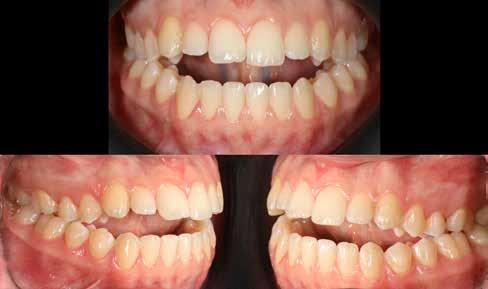

Lány páciensem I. fázisú kezelését 10 évesen kezdtük el bimaxilláris funkciós, kivehető készülékkel. Megfigyelhetőek a class 2-es eltérésnél tipikusan jellemző szűk felső és alsó fo-

gívek, valamint a nagy overjet, a mandibula disztál helyzete, továbbá a felső metszőfogak protrúziója, amelynek kialakulásához sokszor hozzájárul az ujjszopás is (1-3. képek)

A vegyes fogazati kezelési célok a fogívek tágítása és a mandibula meziális irányú növekedésének a biztosítása volt. Fontos, hogy az ilyen típusú készülékeket nem csak éjszaka, hanem napközben is – amennyit csak lehet – hordani kell a minél hatékonyabb működés érdekében. A 18 hónapos első fázisú kezelésnek köszönhetően az alap kezelési célok megvalósultak, sikerült a class 1-es okklúziót beállítani (4-7. képek).

Abban az esetben, amikor az első fázisú kezelési célok elérése megtörtént, de még nem törtek elő a maradó fogak az első moláristól az első molárisig – mintegy passzívan, csak éjszakánként hordva –, tovább folytatjuk a funkcionális kivehető készülék viselését.

Esetünkben 18 hónap után a maradó fogazat előtörése megtörtént, így rögtön folytathattuk a fogszabályozást.

A második fázisú kezelés Pitts-21-es fix fogszabályozó készülék alkalmazásával történt meg. A Pitts elveknek megfelelően a kezelési célok a felső középső metszőfogak megfelelő pozicionálása, a 12 fogas (6-ostól – 6-osig) mosoly, az ideális íves lefutású mosolyvonal kialakítása, továbbá az okklúzió finomítása voltak. Mint mindig, a felső fogíven mosolyvonal beállító esztétikai pozicionálást (Smile Arc Protection - SAP) alkalmaztunk, a mes-

terséges harapásemelés pedig az alsó hatosokra, majd később a felső négyesekre került (8. kép). Az intermaxilláris elasztikus gumihúzás class-2-ess vektorú volt annak érdekében, hogy a disztálharapás korrekciója tökéletes legyen (9. kép). A harapást beállító elasztikus gumihúzásokat – mint minden kezelésnél –, ebben az esetben is folyamatosan, az egész kezelés alatt 24 órában (étkezések kivételével) viselte páciensünk.

A második Pitts-21 fix készülékes fázis ideje 16 hónap volt (10-12. képek)